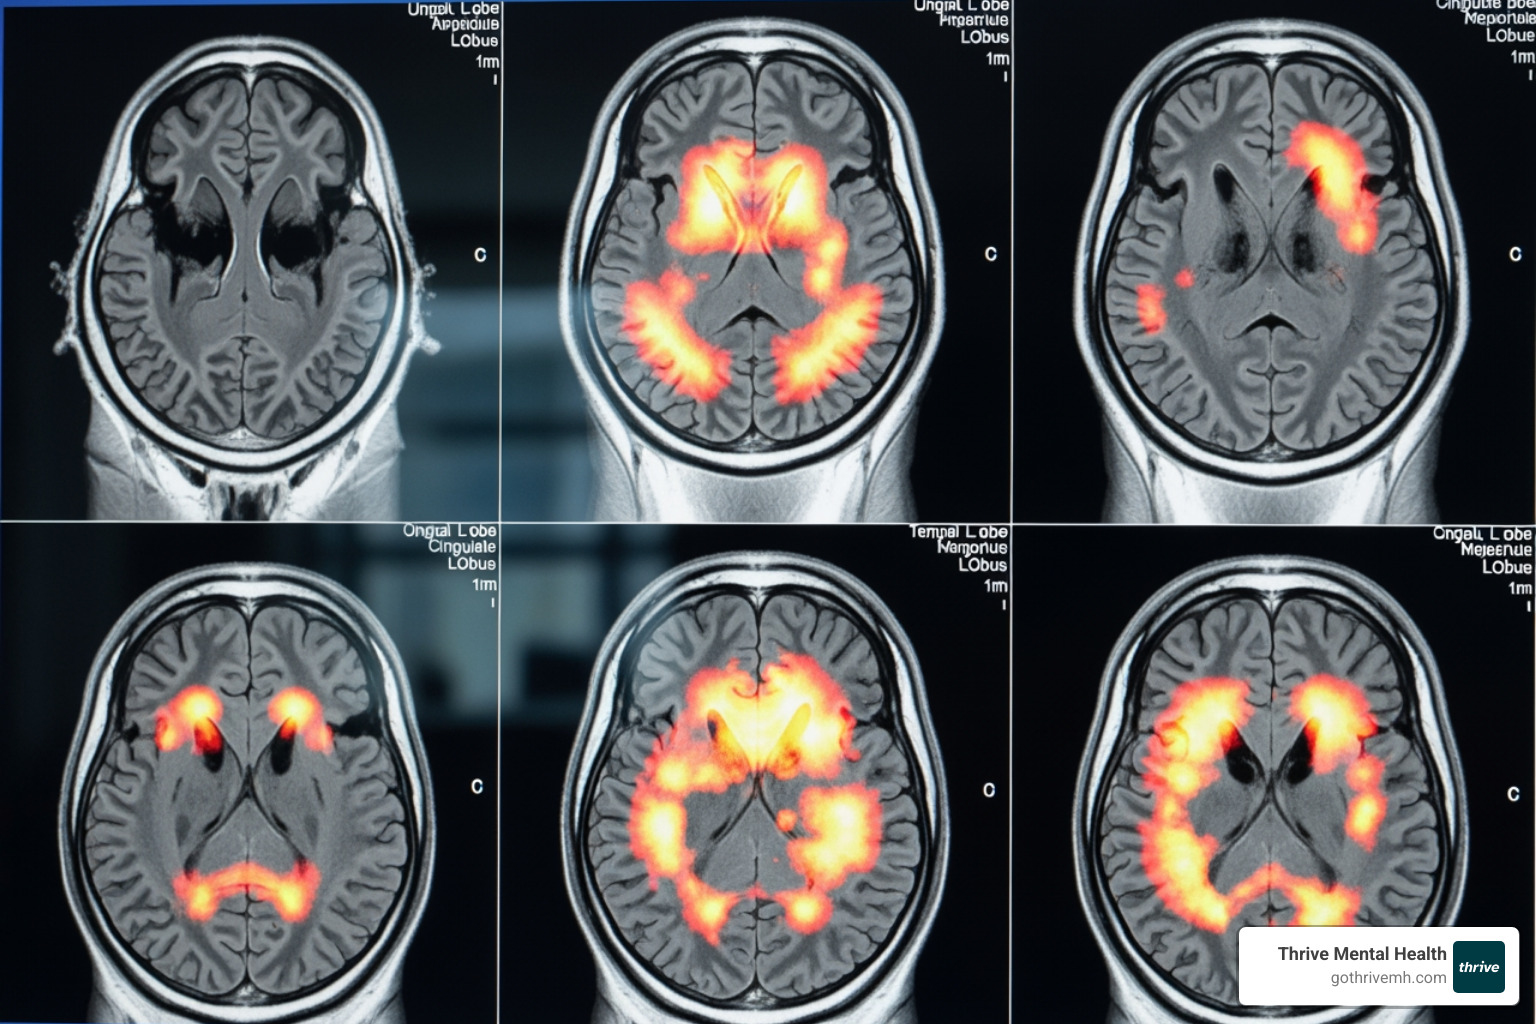

The science backs this up. Neuroscience research shows that creative tasks activate brain regions responsible for emotion and memory, inducing a state similar to meditation. This addresses mental health challenges at a neurological level, making it a powerful tool for young professionals dealing with performance anxiety and burnout.